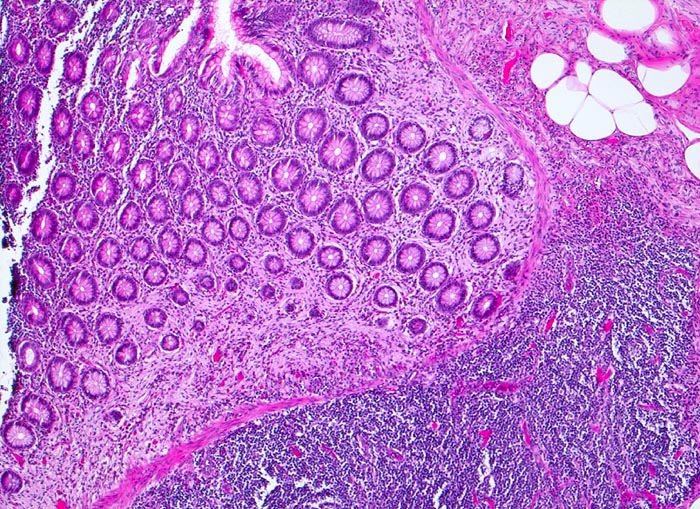

PathoPic – image database / PathoPic ID 3393 - neurogene Appendikopathie Mukosaform

neurogene Appendikopathie Mukosaform

Appendix vermiformis

In den basalen Abschnitten ersetzt auffallend helles lockeres Gewebe die Kolonkrypten (proliferierte Nervenfasern).

Die neurogene Appendikopathie existiert in einer intramucosalen Form, als zentrales Neurom in einer narbig obliterierten Appendixspitze oder als neuromuskuläre Proliferation in der Submucosa.